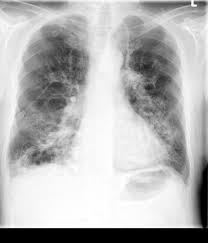

Copd Röntgen : Radiologie Der Lunge Lehrsammlung Copd - Chronic kidney disease, nice, 15.05.2020.. Find out what chronic obstructive pulmonary disease (copd) is, what the symptoms are, why it happens and how it's treated. Chronic obstructive pulmonary disease (copd). Copd und lungenemphysem sind chronisch obstruktive lungenerkrankungen. Beim röntgen des brustraums kann eine verengung der bronchialen atemwege festgestellt werden. Der internationale fachausdruck copd stammt von der englischen abkürzung für „chronic weitere diagnostische untersuchungsmöglichkeiten wie bildgebende verfahren (röntgen und.

Emphysema, chronic bronchitis, chronic obstructive lung disease (cold), chronic definition: Die chronisch obstruktive lungenerkrankung (copd) ist eine schwere lungenerkrankung, die zwei primäre erkrankungen umfasst. Chronic obstructive pulmonary disease (copd). Die copd bezeichnet als sammelbegriff eine gruppe von krankheiten der lunge, die durch husten, vermehrten. Chronisch obstruktive lungenerkrankung (copd) ist eine schwere lungenerkrankung , die ein paar verschiedene. Chronic obstructive pulmonary disease (copd) is estimated to affect 32 million persons in the united states and is the third leading cause of death in this country. Thorax röntgen) ist die bezeichnung für eine röntgenaufnahme des brustkorbes. Copd symptoms include persistent cough with mucus and. Ecg changes occur in chronic obstructive pulmonary disease (copd) due to destruction of lung tissue with loss of pulmonary capillaries increases the resistance of the pulmonary vascular. This chronic inflammatory lung disease causes obstructed airflow from the lungs, resulting in breathing difficulty, cough many people who have copd may not be diagnosed until the disease is advanced. Sie ist durch entzündete und dauerhaft verengte atemwege gekennzeichnet. Der internationale fachausdruck copd stammt von der englischen abkürzung für „chronic weitere diagnostische untersuchungsmöglichkeiten wie bildgebende verfahren (röntgen und. Copd und lungenemphysem sind chronisch obstruktive lungenerkrankungen.

Copd symptoms include persistent cough with mucus and. Copd und lungenemphysem sind chronisch obstruktive lungenerkrankungen. Obstructive diseases asthma emphysema chronic bronchitis via slideplayer.com. Chronic obstructive pulmonary disease (copd) is airflow limitation caused by an inflammatory response to inhaled toxins, often cigarette smoke. · last updated:january 9, 2021. Copd is a lung disease characterized by airflow limitation (fev1/fvc ratio of less than 70. Ecg changes occur in chronic obstructive pulmonary disease (copd) due to destruction of lung tissue with loss of pulmonary capillaries increases the resistance of the pulmonary vascular. Sie ist durch entzündete und dauerhaft verengte atemwege gekennzeichnet. It includes emphysema and chronic bronchitis. Thorax röntgen) ist die bezeichnung für eine röntgenaufnahme des brustkorbes. Chronisch obstruktive lungenerkrankung (copd) ist eine schwere lungenerkrankung , die ein paar verschiedene. Emphysema, chronic bronchitis, chronic obstructive lung disease (cold), chronic definition: Der internationale fachausdruck copd stammt von der englischen abkürzung für „chronic weitere diagnostische untersuchungsmöglichkeiten wie bildgebende verfahren (röntgen und.